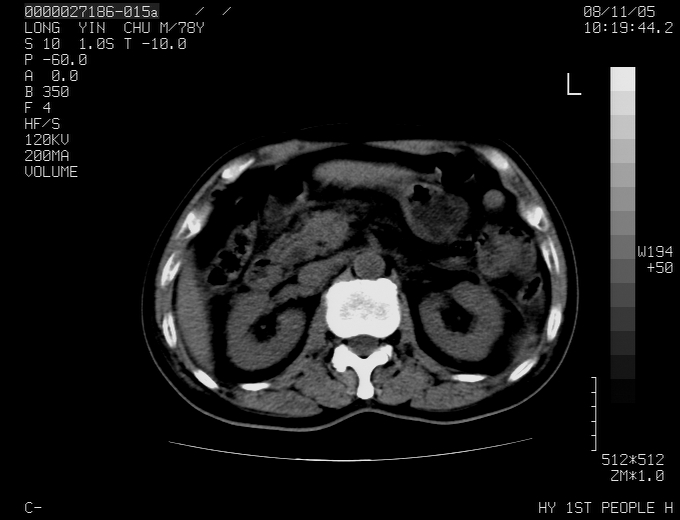

标题: CT16532:M78Y,肝脏病变,请会诊 [打印本页]

标题: CT16532:M78Y,肝脏病变,请会诊

腹胀,腹痛就诊,男性,78岁,外院b超未见异常。

肝ca,脾肾转移

支持脾肾转移瘤,双侧胸腔积液。

考虑弥漫性肝癌并脾及双肾转移.双侧胸水.

图片质量欠佳:多考虑:左侧肾癌。脾脏转移!胸膜转移!

考虑弥漫性肝癌并脾及双肾转移.双侧胸水.  支持

肝脾肾转移瘤可能性大,左肾不除外梗塞,双侧胸水

考虑弥漫性肝癌并脾及双肾转移,双侧胸水。

考虑肝癌并双肾及脾脏转移;双侧胸腔积液。